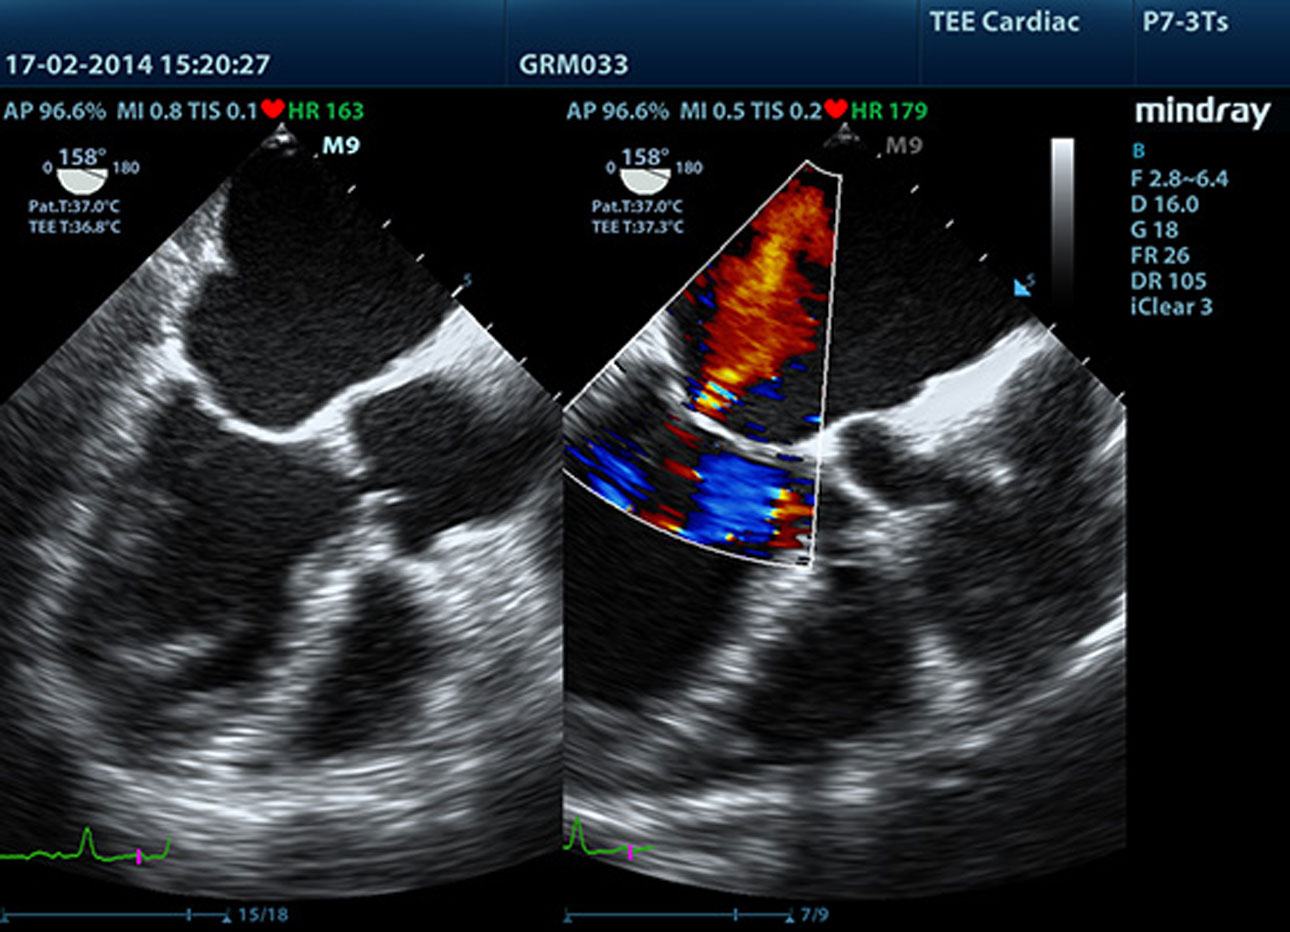

TDI (Doppler tkankowy)

Obrazowanie Tkanek z u?yciem Dopplera - Tissue Doppler Imaging pozwala na ilo?ciow? ocen? miejscowego ruchu i funkcji mi??nia sercowego. Aparat M9 zapewnia kompletny tryb Dopplera tkankowego w celu uzyskania szybszej i bezpo?redniej diagnozy.

LVO z badaniem wysi?kowym

Mo?liwo?ci premium systemu M9 pozwalaj? na zwi?kszenie kontrastu lewej komory podczas badań wysi?kowych, wzmacniaj?c rozró?nienie pomi?dzy tkank? mi??nia sercowego a przep?ywem krwi. Umo?liwia to lepsz? wizualizacj? wsierdzia. Funkcja Stress Echo w aparacie M9 obejmuje kompletny pakiet dla obci??enia farmakologicznego i?wysi?kowego. Pakiet ten jest wspierany przez elastyczny system raportowania, który mo?na dostosowa? do Państwa indywidualnych potrzeb.